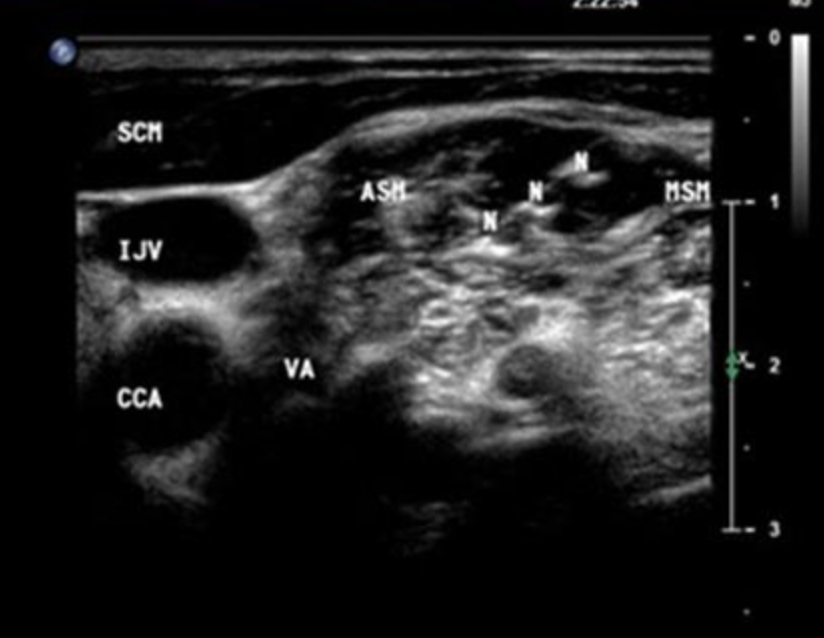

Name the structures seen in this US of the lateral neck

N – Nerve

IJV – Internal jugular vein

CCA – Common carotid artery

VA – Vertebral artery

ASM/MSM – Anterior/middle scalene muscle

SCM – Sternocleidomastoid